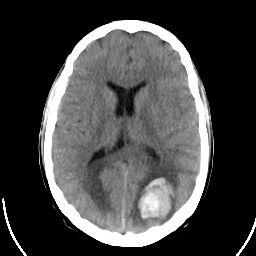

Sarcoma: Roentgen-ray CT -- Slice #13

[Home][Help][Clinical] Slice 13